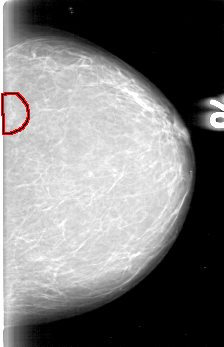

D_4003_1.LEFT_CC

LEFT_CC LINES 5191 PIXELS_PER_LINE 3346 BITS_PER_PIXEL 12 RESOLUTION 43.5 OVERLAY

FILE: D_4003_1.LEFT_CC.OVERLAY

TOTAL_ABNORMALITIES 1

ABNORMALITY 1

LESION_TYPE MASS SHAPE IRREGULAR MARGINS OBSCURED

ASSESSMENT 0

SUBTLETY 4

PATHOLOGY BENIGN

TOTAL_OUTLINES 1

BOUNDARY